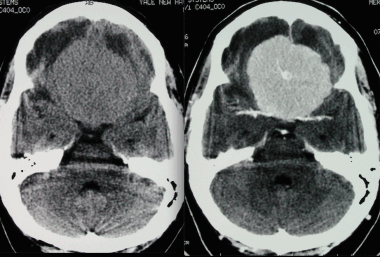

4) Метастазы собственно в головной мозг, в паренхиму головного мозга.

- 80% всех вторичных опухолей локализуются в полушариях мозга

- 15% в мозжечке

- 5% в мозговом стволе

Признаки метастазов мозга на КТ

- Может наблюдаться гиперденсный геморрагический компонент различной степени выраженности.

- Накапливающее контраст объемное образование с отсутствием «доброкачественного» склеротического ободка.

- Метастазы могут выглядеть как накапливающие контраст двояковыпуклые объемные образования, смещающие головной мозг.